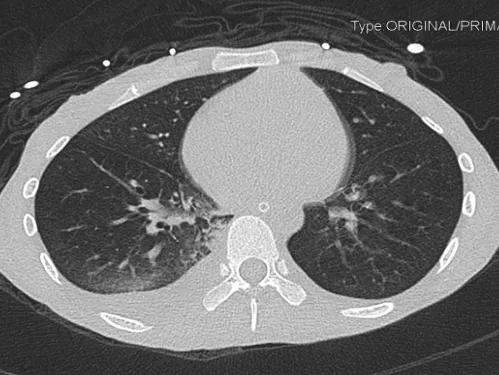

2021-4-29 CTPA:肺动脉干、左右肺动脉及其分支未见狭窄及明显充盈缺损。右肺、左肺下叶见斑片影、磨玻璃影及实变影。

胸部CT:

右肺感染吸收,双侧胸腔积液吸收,双肺散在小结节,多系炎症,左膈抬高。

患者青年女性,慢性病程;主要表现为腹胀、呼吸困难,术后出现意识障碍、II型呼吸衰竭。经呼吸机辅助呼吸、对症支持等治疗后,患者意识恢复但呼吸困难无明显改善;既往有有粉尘接触史。查体见患者极度消瘦、营养不良,双肺呼吸音粗,可闻及散在湿啰音。血气示II型呼吸衰竭、高碳酸血症,轻度贫血,低蛋白血症,电解质紊乱,炎症指标、肌酶、BNP升高,院外腹水检查示漏出液,未见肿瘤细胞;胸部CT:双肺斑片影,抗感染治疗后病灶吸收;腹部增强CT:双侧附件区分别混杂密度团块影,内见多发囊泡影;心脏彩超:右心稍大,重度肺动脉高压。